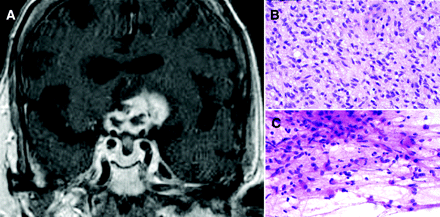

一位79岁的妇女与亚急性急诊科,连续的,严重的视觉神经病变和脑病。她被治疗疑似巨细胞动脉炎在外部设施几个月前(升高红细胞沉降率和最小左视神经增强)。对我们评价她panhypopituitarism和一个大型的、钆增强光学仪器质量扩展通过下丘脑和额叶(图)。活检诊断等级IV纤丝的星形细胞瘤(多形性成胶质细胞瘤;图,B和C)。视神经胶质瘤通常是低级和诊断的童年,而罕见的成人病例往往是高档胶质母细胞瘤是在目前的情况下。1,2

图

(一)冠状T1 postgadolinium MRI显示不均匀增强质量集中上水箱内涉及光学仪器和下丘脑扩展优涉及额叶低劣。(B, C)活检标本组织学部分显示hypercellular纤丝的恶性肿瘤与中度细胞异型性和罕见的凋亡体(原始hematoxylin-eosin污点,400×放大)。